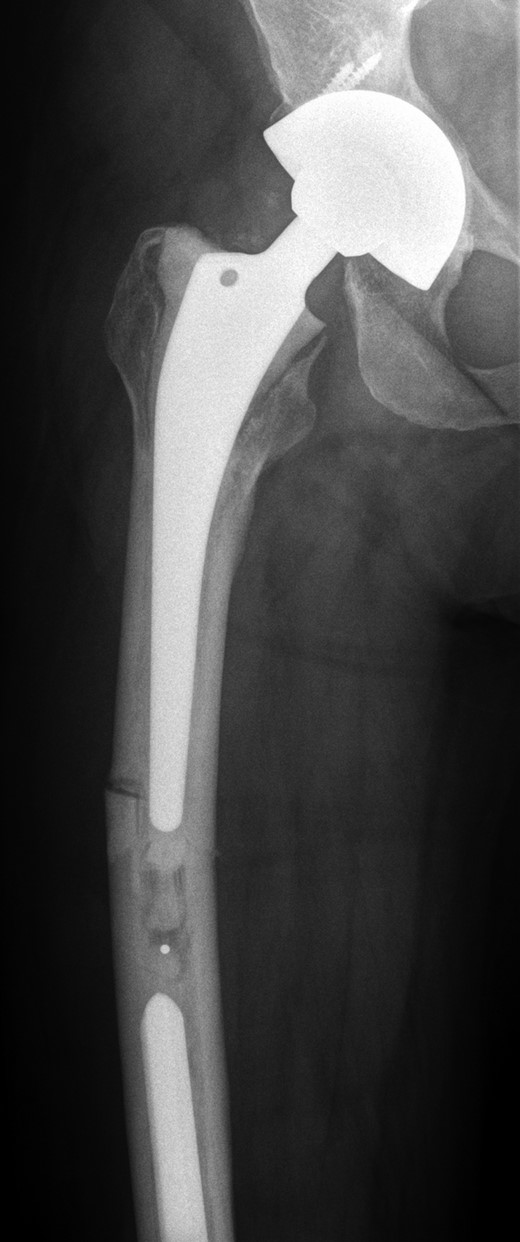

She subsequently sustained a periprosthetic fracture at the distal tip of her right total hip replacement (Fig. 1). An initial attempt was made to manage this fracture with a plate and Dall-Miles cables (Fig. 2); however, the fracture did not unite. The patient went on to have a custom-made cement-linked internal proximal femoral replacement, which had a hollow cylindrical design to accept the stem of the existing well-fixed distal femoral component (Figs 3 and 4). This linked prosthesis effectively converted her separate prostheses to a total femoral replacement, sparing her distal femoral replacement from revision. She had no problems postoperatively and recovered well from her surgery.

Plate and Dall-Miles cable fixation of periprosthetic fracture.